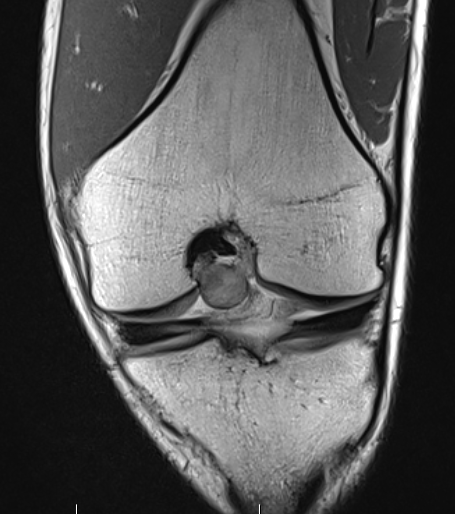

MRI

Synovial thickening

Hemosiderin

- low signal intensity on TI and T2 - "drop out" signals

- blooming on gradient echo

Localized PVNS of the notch

Localized posterolateral PVNS

Diffuse

Diffuse PVNS with involvement of suprapatella pouch and posterior compartments, including posterior extra-articular

Severe diffuse PVNS with bony involvement